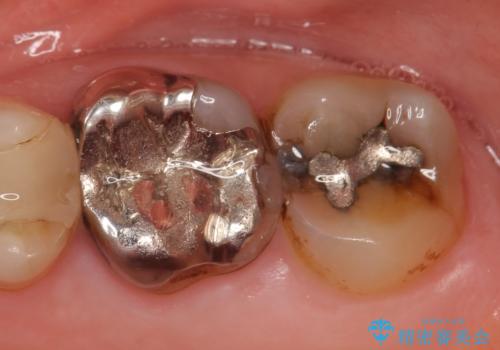

- 左上6番目の歯が欠けてしまったので診て欲しいといらっしゃった方の症例です。

左上6番目は銀歯・虫歯を除去後、オールセラミッククラウンにて補綴を行いました。

左上7番目も虫歯だったため、銀歯・虫歯を除去後、セラミックインレーにて修復を行いました。